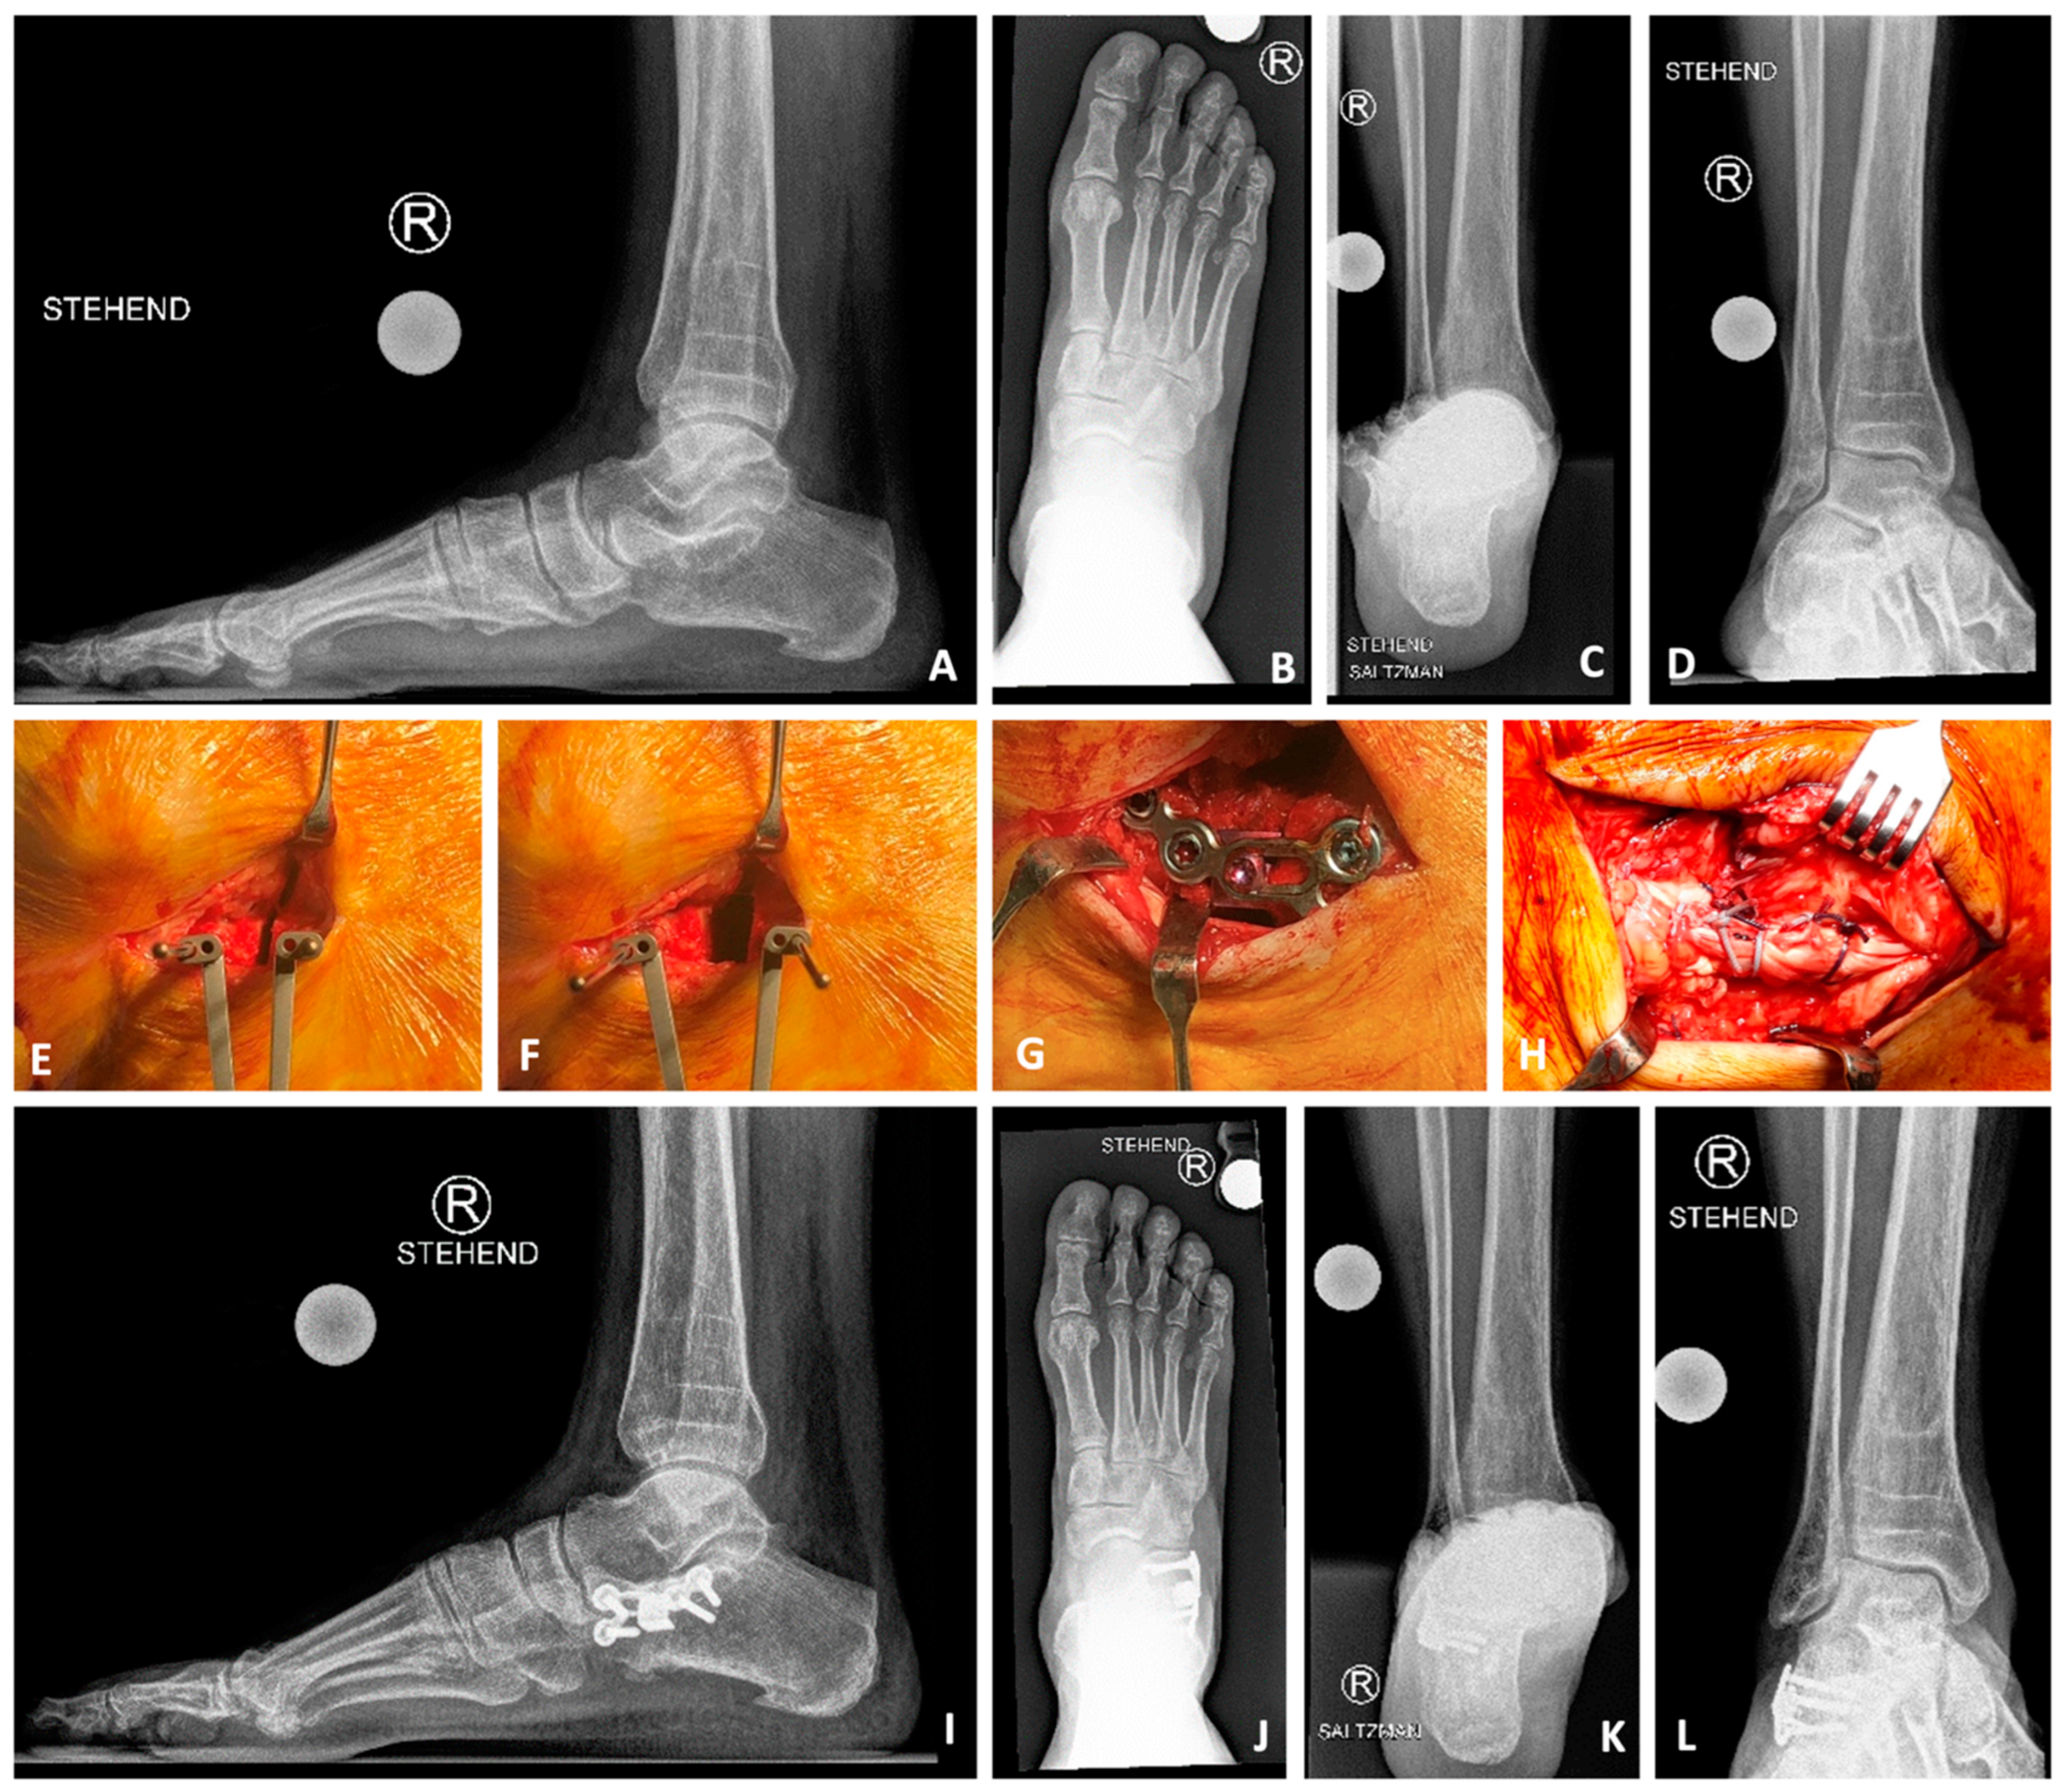

Figure 5. Lateral calcaneal lengthening osteotomy (LCLOT) with anatomical plate and titanium wedge. Sixty-four-year-old male with painful severe pes planovalgus and abductus right foot due to posterior tibial insufficiency with deltoid and spring ligament lesion. Treatment by LCLOT with anatomic Aptus-LCLOT-Plate (Medartis, Basel, Switzerland) and deltoid/spring ligament reconstruction as well as flexor digitorum longus (FDL) to posterior tibial (PT) tendon transfer. (AD) preoperative X-rays: lateral foot, AP foot, Saltzman view, mortise view, (EH): intraoperative pictures ((E) LCLOT with K-wire-forceps, (F) open of the LCLOT; (G) Aptus-LCLOT-Plate with titanium-wedge (Medartis, Basel, Switzerland) and spongiotic iliac-crest-autograft; (H) medial soft tissues reconstruction); (IL) postoperative X-rays: 6 months postoperative with three-dimensional improvement of foot position and painfree patient.